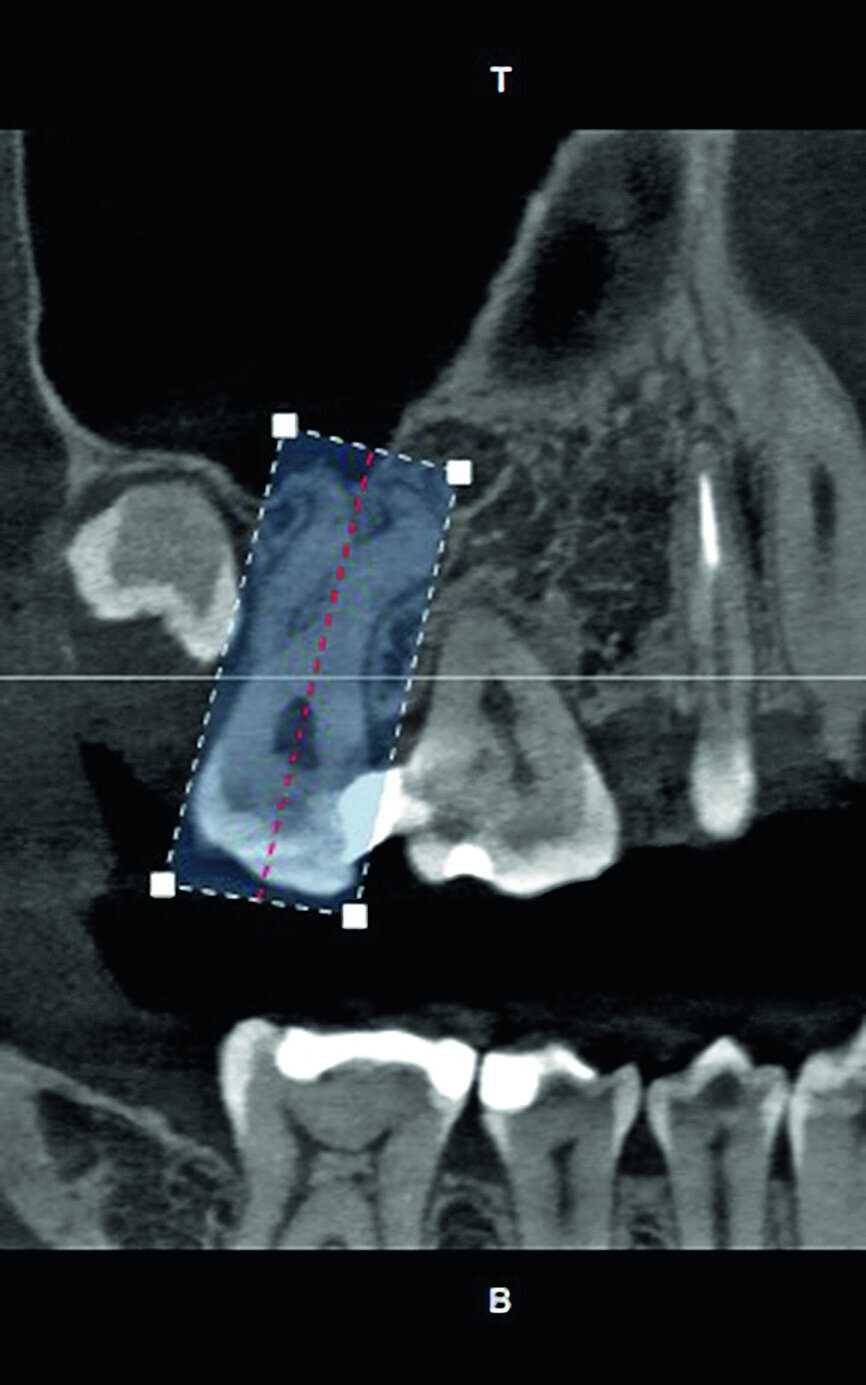

The patient, a 25-year-old female, reported with irreversible pulpitis on her maxillary second left molar. The tooth was temporarily restored with Intermediate Restorative Material (IRM, Dentsply Sirona) and the patient complained about continuous food impaction between her maxillary left, first and second molar teeth (Fig. 2). A periapical radiograph revealed that the temporary restoration was not sealing at the gingival margin (Fig. 3). Also, visible on the periapical radiograph was evidence of possible curvatures in the mesiobuccal and distobuccal roots. It was decided, with the consent of the patient, to take a limited field of view CBCT scan to explore the anatomy of this tooth. The CBCT scan revealed the presence of three root canal systems when viewed in the axial plane; and in the sagittal plane, evidence of severe root curvatures were present in the mesiobuccal and distobuccal root canal systems. It was decided to do a more in-depth investigation as a result of this complex anatomy, using the 3D Endo Software (Dentsply Sirona).

In the first step, ‘Diagnosis and Pathology’, the imported scan was reviewed in the axial, sagittal and coronal planes. The software has the ability to present a 3-D reconstructed view where the transparency of the teeth can be changed (Figs. 4a–d).

The second step, ‘3D Tooth Anatomy’, involved selecting the tooth to be examined and the entire volume was cropped to only leave the data of interest behind (Fig. 5). In the third step, ‘Canal System’, the number of root canals were identified and each root canal was then mapped separately by identifying the orifice and radiographic apical foramen of each root canal (Fig. 6).

With the fourth step, ‘3D Canal Anatomy’, the software made a proposal of the canal anatomy (Fig. 7), but the operator can make corrections according to the canal configuration that can be viewed in different planes in the software. Figures 8 to 10 show the mapping of the palatal, mesiobuccal, and distobuccal root canal systems.

During the fifth step, ‘Treatment Plan’, the software projected ISO size 06 instruments into the canals (Fig. 11), which allowed the operator to visualise the internal anatomy of the canals, check straight line access, and modify the proposed access if necessary. A rubber stop on the files can then be digitally adjusted to a coronal reference point of choice that will then indicate the proposed working length for each root canal system. This view can also be rotated in 3-D to alert the operator of the angle and direction of curvatures in the root canal systems (Fig. 12). The step after ‘treatment plan’ is to select a master file from a preloaded database of endodontic file systems that will most likely result in optimal canal preparation for that specific shape or diameter of a canal. Considering the s-shaped curvatures in all three root canal systems as well as the sharp curvatures in different planes, it was decided to use the Primary WaveOne Gold file (25/07) in the palatal canal and the Small WaveOne Gold file (20/07) for root canal preparation in the two-challenging buccal root canal systems (Fig. 13). The selected instruments were then displayed in the root canal systems and the operator again digitally rotated and visualised the root canal anatomy in 3-D (Fig. 14).